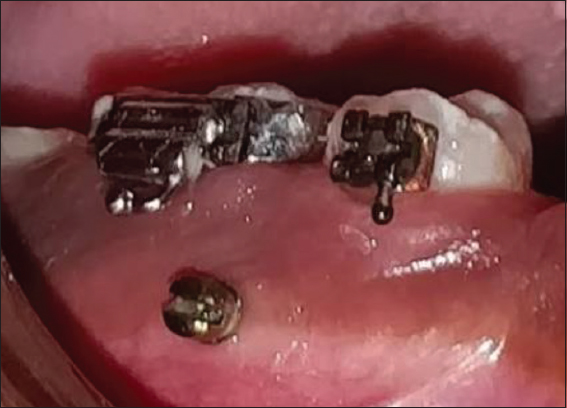

Next, the titanium grade V self-drilling micro-implants of diameter 1.5 mm and length 6 mm[24] [Figures 2 and 3] were inserted in such a way as to obtain maximum insertion depth and an angulation of 90°. An intraoral periapical radiograph was taken to ensure that the micro implant angulation is satisfactory and to confirm that the adjacent roots were not injured [Figure 4].

thumb

Figure 2: Micro-implant of length 6 mm and diameter 1.5 mm

Figure 3: Micro-implant placed between 45 and 46